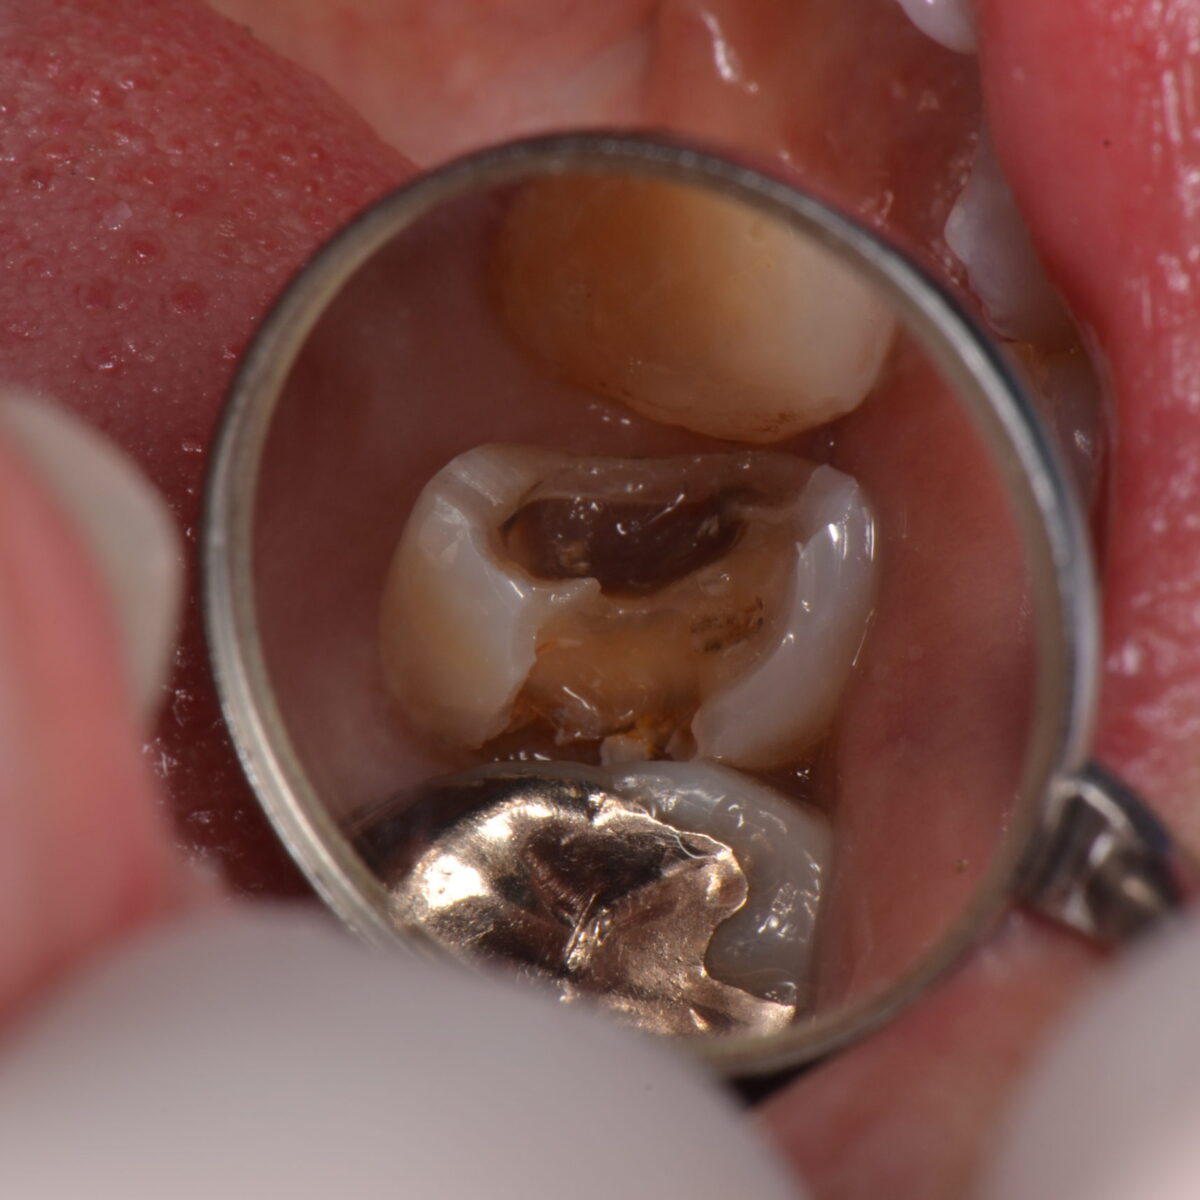

銀歯の下には・・・2

【東京メトロ東西線妙典駅 徒歩5分の歯医者】市川、妙典の歯科医院、めぐりデンタルクリニックの梶原です。 時々載せる銀歯シリーズ。一つだけお断りをしておくと、すべての銀歯で問題が起こ…